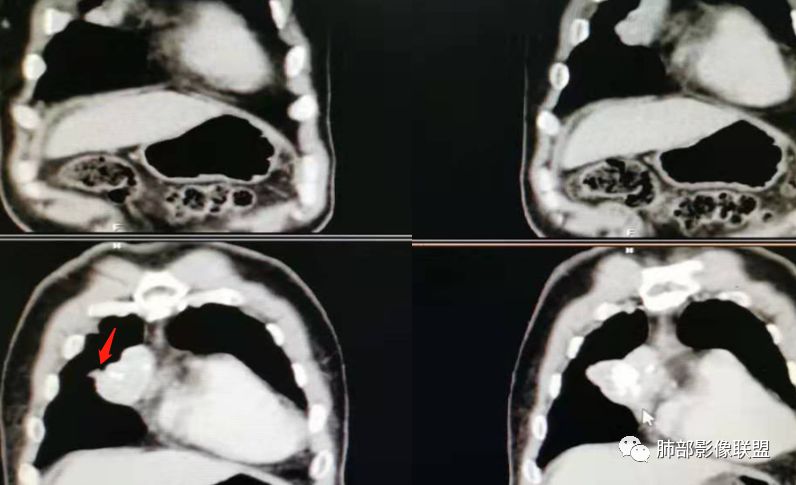

实性部分密度与肌肉类似,钙化粗大、结节状

右侧内乳动脉增粗

实性部分中度强化——增加20~27HU

深分叶,边界尚清,附近未见肿大淋巴结

1.CD钙化不支持,一般条状短棒状为主,小结节

也有,这么大的钙化少见,分叶也太明显。

2.异位甲状腺:发病率低,强化太弱,一般来说异位甲状腺强化达100多

3.神经鞘瘤:深分叶,这么大钙化罕见

所以胸腺瘤首选,其次畸胎瘤,SFT

胸腺瘤